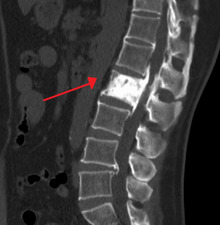

An ivory vertebra due to probable Paget disease

The first clinical manifestation of Paget's disease is usually an elevated alkaline phosphatase in the blood.[5]